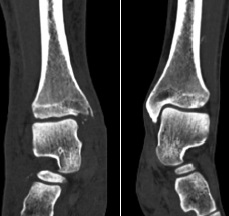

The patient underwent a CT study of the ankle joints with subsequent 3D reconstruction to mo-del the shape of the medial malleolus (Fig. 2, 3).

Fig. 2. CT scans of both ankle joints after primary surgical debridement